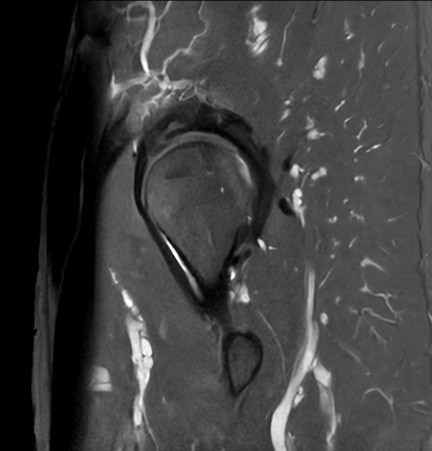

Fast bilateral hips, with SmartSpeed Precise

Used Solution